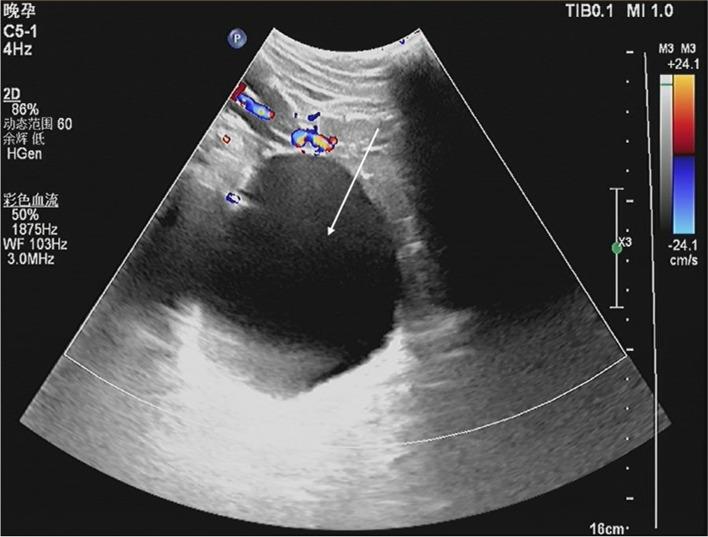

We present a multigravida with breech presentation at 37 weeks of pregnancy in whom a large pelvic hydatid cyst and multiple hepatic hydatids were diagnosed by ultrasonography. The large pelvic hydatid cyst was drained through the posterior fornix under the guidance of ultrasound, and an external cephalic version was performed. A healthy baby was delivered vaginally with head presentation at term.

我们报告了一例妊娠 37 周、臀位的多产妇,超声检查诊断为巨大盆腔包虫囊肿和多个肝包虫。在超声引导下,通过后穹窿引流了巨大的盆腔包虫囊肿,并进行了外部胎头倒转术。足月时,阴道分娩了一个头位的健康婴儿。